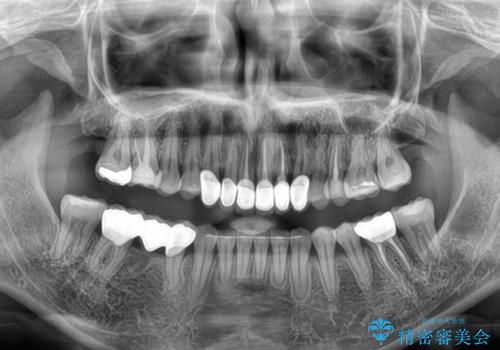

矯正治療自体はインビザラインで満足のいく仕上がりとなりました。

前歯は根管治療が必要となり、元々舌側に入り込んでいた左上2番目の歯は歯周外科処置により歯肉ラインを整えることとしました。

欠損部位は傾斜歯軸を起き上がらせることができたため、オールセラミッククブリッジにて補綴治療を行いました。

全顎的に満足のいく仕上がりとなりました。